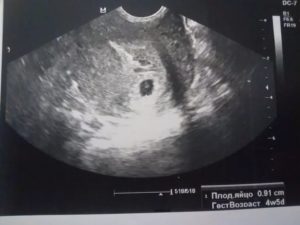

Описание плодного яйца

Плодное яйцо — это защитные оболочки, окружающие зародыш. Они прикрепляются к стенке матки, образуя с ней сосудистую связь. Через сосуды растущий зародыш получает питание из материнской крови. Плодное яйцо на УЗИ выглядит, как округлое образование темно-серого цвета.

Оно становится видным, когда достигает размера 5 мм. Это соответствует 4 неделям беременности. Эмбрион внутри яйца пока не виден. Его можно рассмотреть после 35-го дня, выглядит он как темная полоска. Части его тела можно увидеть на 12 неделе беременности — в этот срок обычно и проводят первое обследование.

Размеры плодного яйца по неделям

По размерам зародыша определяют срок беременности с точностью до 2-3 дней. До полутора месяцев дату родов определяют по ДПП — диаметру плодного яйца. Диаметр измеряют в самой широкой части по трем разным плоскостям. Для вычисления даты родов есть специальная таблица.

Такой критерий, как СВД — средний внутренний диаметр — определяет дату родов не очень точно. После 6 недели, когда на УЗИ появляется эмбрион, срок определяют по КТР — копчико-теменной размер. Изображение эмбриона измеряют продольно. Размеры с 6 по 8 недели: